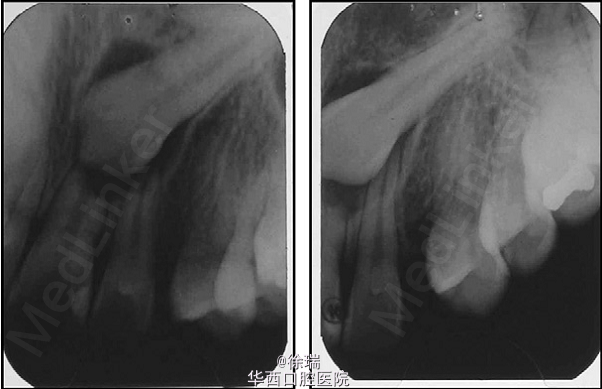

尖牙的异位萌出多见于上颌,可造成相邻牙齿的根尖吸收。最近遇到了一个病例,15岁的女孩儿,安氏III类,上颌尖牙阻生,因为尖牙的位置太过靠近侧切牙和中切牙根方,邻牙发生了严重的根尖吸收。那这样的病情又该如何矫正呢?